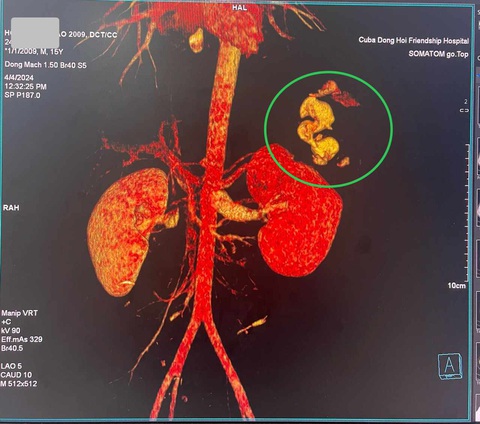

Chụp CT scan thấy tổn thương ở lách độ I - II. Chấn thương rách cực trên thận ổ lớn, xuyên vào nhu mô thận, đứt mạch máu gây chảy máu ồ ạt thành vòi - Ảnh: Đ.HÙNG

Kết quả CT scanner cho thấy em B. bị đâm thủng thận trái độ IV xuyên tới đài thận, có ổ đang chảy máu ồ ạt thành vòi và chấn thương lách độ I-II.